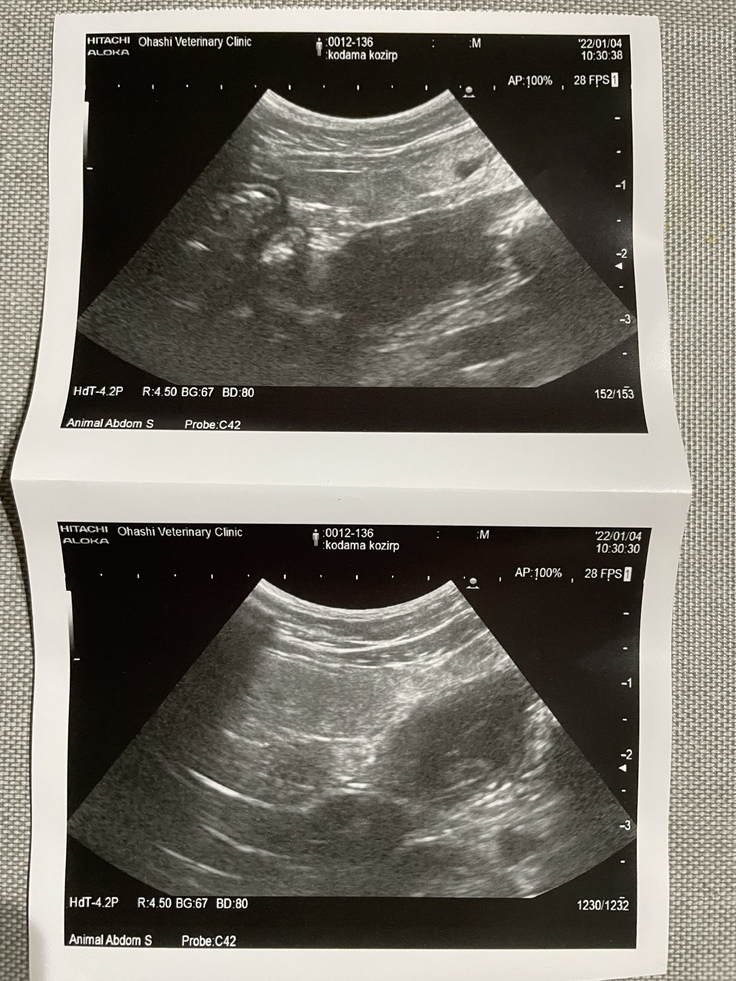

転院先で再度診察していただいたところ、大腿骨の骨折と骨盤のズレ、膀胱が腫れており血尿が出ているとのことでした。

命に関わるため最優先で大腿骨骨折の手術が必要で、骨盤は様子を見て必要であれば改めて手術、膀胱は破裂してしまった場合は手術で様子見ということになりました。

◾️1/4 初回の診療

レントゲン撮影と血液検査をしました。

大腿骨の骨折で手術が必要とのことです。